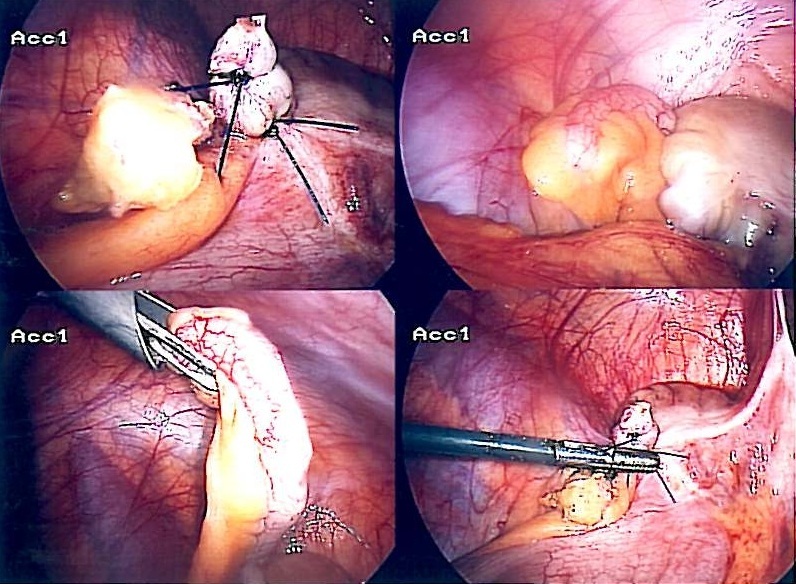

Management typically involves appendicectomy, which can be performed via open or laparoscopic approach, with laparoscopic appendicectomy being the treatment of choice.

Laparoscopic Appendicectomy is becoming increasingly popular